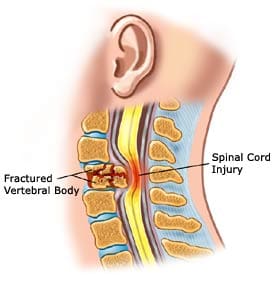

After a car crash, compression fractures are common in the thoracic and cervical spine (middle and lower back). While the entire body is held in place with a seatbelt, the body may be thrown forward during impact. This can pull on the vertebrae. As the vertebrae may rarely move, in some cases, spinal fractures may result in spinal cord injuries. Those with spinal cord injuries may experience tingling, numbness, weakness, or bowel and bladder control loss. However, the main symptom of a spinal fracture is mild to severe back pain that interferes with movement. When a fracture is suspected, it is essential not to move the injured person; harm could be caused by motion.

Spinal Fractures

Spinal Fractures